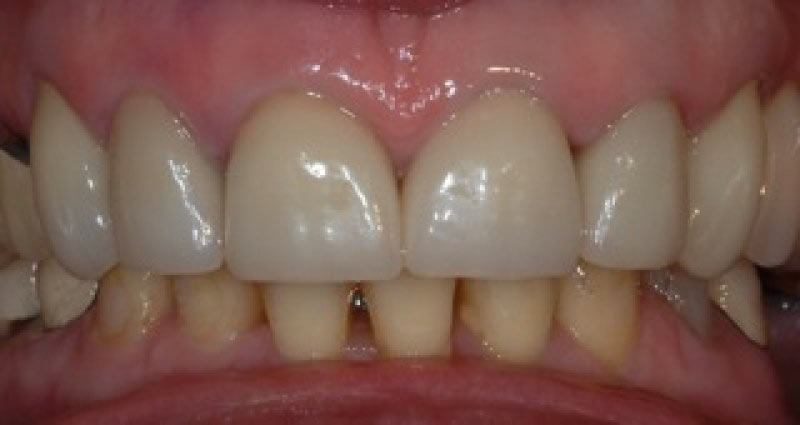

Upper crowns and lower composites (4 images)